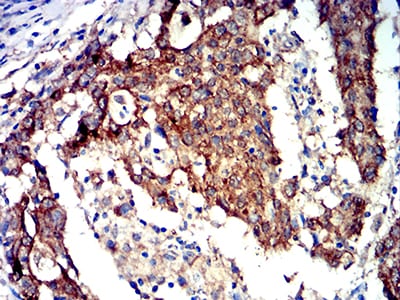

Immunohistochemical analysis of paraffin-embedded human stomach cancer tissues using PRKAA2 mouse mAb with DAB staining.